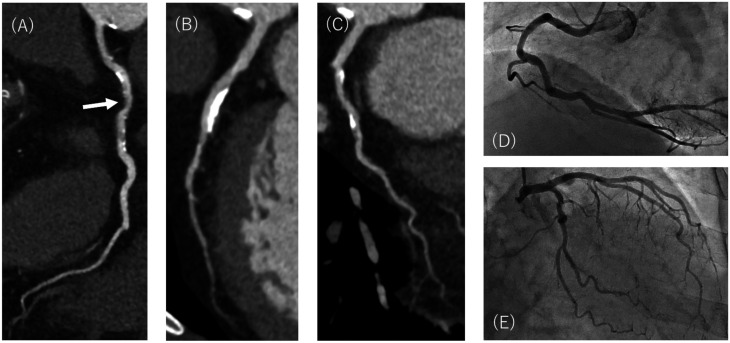

Purpose: To compare the objective and subjective image quality and diagnostic performance for coronary stenosis of normal-dose model-based iterative reconstruction and reduced-dose super-resolution deep learning reconstruction in coronary CT angiography.

Materials and methods: This single-center retrospective study included 52 patients (mean age, 68 years ± 10 [SD]; 41 men) who underwent serial coronary CT angiography and subsequent invasive coronary angiography between January and November 2022. The first 25 patients were scanned with a standard dose using model-based iterative reconstruction. The last 27 patients were scanned with a reduced dose using super-resolution deep learning reconstruction. Per-patient objective and subjective image qualities were compared. Diagnostic performance of model-based iterative reconstruction and super-resolution deep learning reconstruction to diagnose significant stenosis on coronary angiography was compared per-vessel using receiver operating characteristics curve analysis.

Results: The median tube current of super-resolution deep learning reconstruction was lower than that of model-based iterative reconstruction (median [IQR], 890 mA [680, 900] vs. 900 mA [895, 900], P = 0.03). Image noise of super-resolution deep learning reconstruction was lower than that of model-based iterative reconstruction (14.6 Hounsfield units ± 1.3 vs. 22.7 Hounsfield units ± 4.4, P < .001). Super-resolution deep learning reconstruction improved the overall subjective image quality compared with model-based iterative reconstruction (median [IQR], 4 [3, 4] vs 3 [3, 3], P = .006). No difference in the area under the receiver operating characteristic curve in diagnosing coronary stenosis using super-resolution deep learning reconstruction (0.96; 95% CI, 0.92-0.99) and model-based iterative reconstruction (0.96; 95% CI, 0.92-0.98; P = .98) was observed.

Conclusion: Our exploratory analysis suggests that super-resolution deep learning reconstruction could improve image quality with lower tube current settings than model-based iterative reconstruction with similar diagnostic performance to diagnose coronary stenosis in coronary CT angiography.